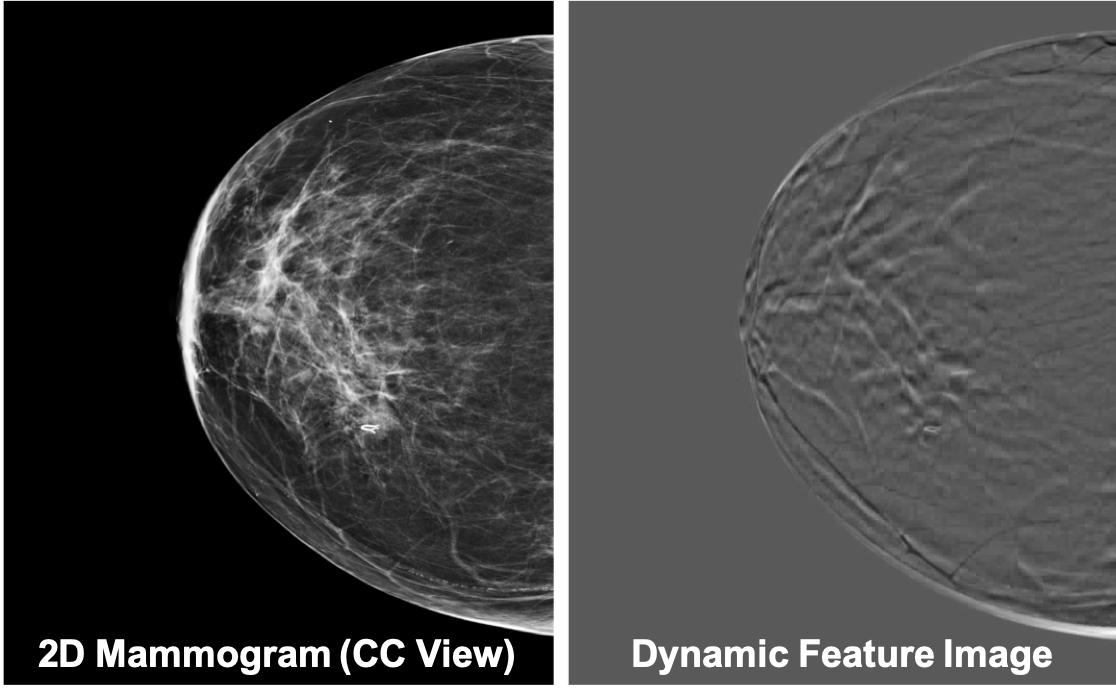

In non-medical domain, a popular method to represent a series of images is to apply a temporal pooling operator to the features extracted at individual images, for instance, temporal templates [21], ranking functions [22] and sub-videos [23], as well as other traditional pooling operators [24]. We adopt the idea of temporal pooling operator to the medical imaging domain. Inspired by Bilen et al., we applied RankSVM [25] directly on DBT data to extract a fixed, one-slice representation of each DBT. Since the extracted fixed representation keeps the dynamic features (i.e., the slice-to-slice changes) of DBT, we call it dynamic feature image. See Figure 2 for an example.

One dynamic feature image is a single RGB image, which captures the slice-to-slice changes of a DBT. A ranking function is used to obtain the dynamic feature image for a series of slices ,…,, temporally. More specifically, let be the feature vector extracted from each individual slices in the series. Let be the average time of these features up to time . The ranking function associates to each time a score , where is a vector of parameters. The function parameters are learned so that the scores reflect the rank of the slices in the series. Therefore, later times are associated with larger scores, i.e. . Learning is posed as a convex optimization problem using the RankSVM function:

| (1) |

The first term in the objective function is a quadratic regularizer used in SVM. The second term is a hinge-loss that counts how many pairs are incorrectly ranked by the scoring function. The optimizer to the RankSVM is written as a function that maps a series of slices to a single vector . Since this vector contains enough information to rank all the slices in the series, it aggregates information from all of them and can be used as a descriptor of a series of slices. The process of constructing is known as rank pooling [26], which can be applied to DBT directly.